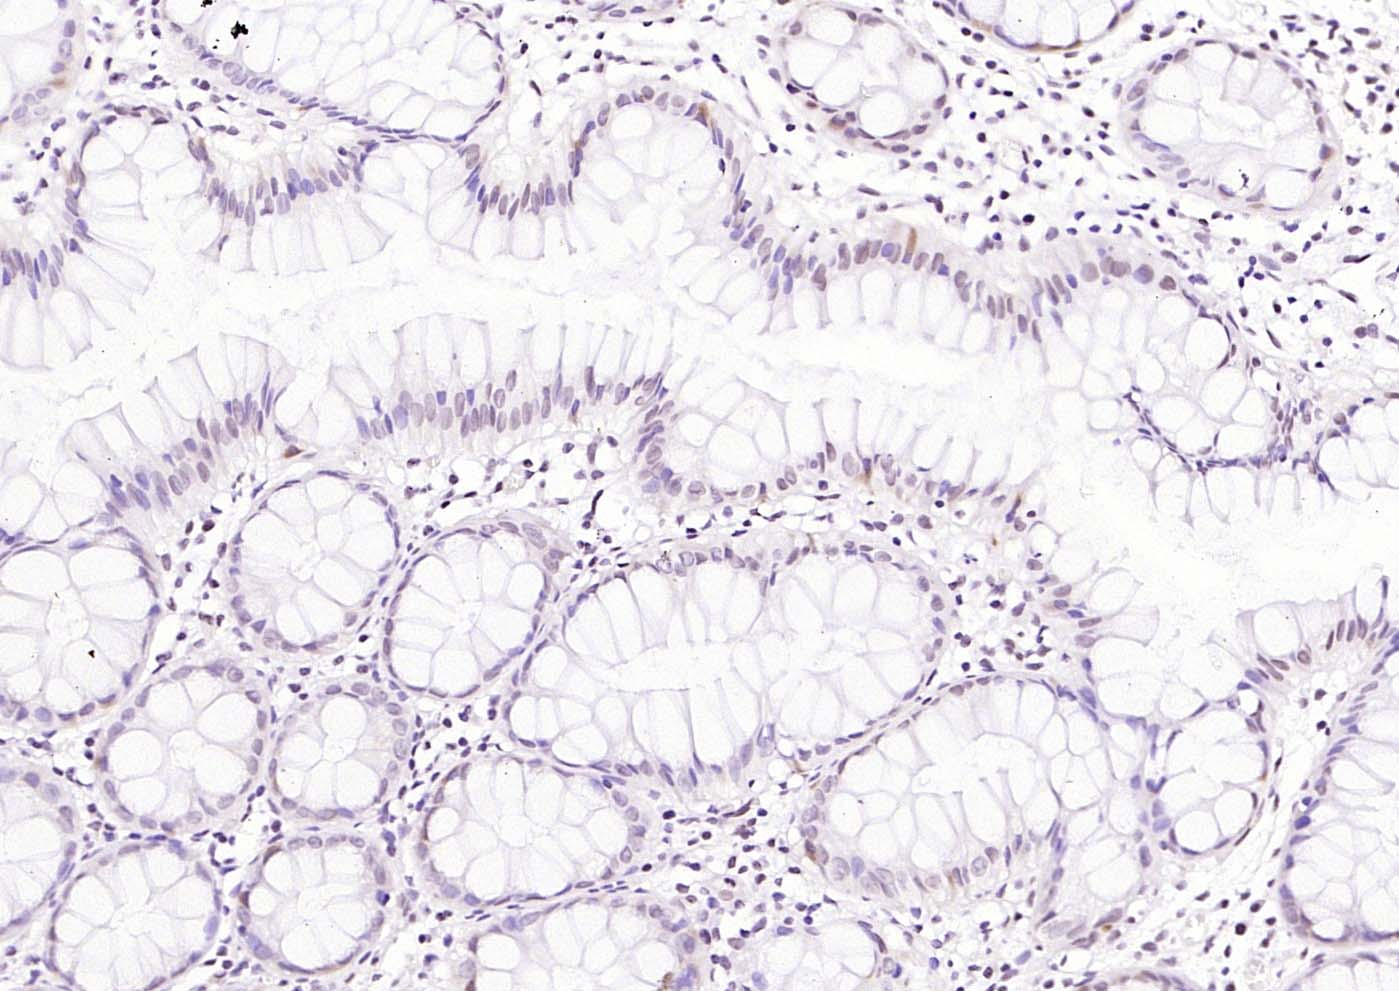

Paraformaldehyde-fixed, paraffin embedded (mouse colon); Antigen retrieval by boiling in sodium citrate buffer (pH6.0) for 15min; Block endogenous peroxidase by 3% hydrogen peroxide for 20 minutes; Blocking buffer (normal goat serum) at 37°C for 30min; Incubation with (CDCA5) Polyclonal Antibody, Unconjugated (bs-7717R) at 1:200 overnight at 4°C, followed by operating according to SP Kit(Rabbit) (sp-0023) instructionsand DAB staining.

Paraformaldehyde-fixed, paraffin embedded (human colon); Antigen retrieval by boiling in sodium citrate buffer (pH6.0) for 15min; Block endogenous peroxidase by 3% hydrogen peroxide for 20 minutes; Blocking buffer (normal goat serum) at 37°C for 30min; Incubation with (CDCA5) Polyclonal Antibody, Unconjugated (bs-7717R) at 1:200 overnight at 4°C, followed by operating according to SP Kit(Rabbit) (sp-0023) instructionsand DAB staining.